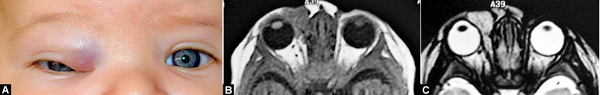

A. Üst kapakta optik ekseni kapayan kapiller hemanjiyom. Ambliyopi nedeniyle acilen tedavisi gerekir. B-C. MR görüntüsü.

Ka­pil­ler he­man­ji­yom ge­nel­lik­le ha­ya­tın ilk haf­ta­la­rın­da gö­rü­lür ve sık­lık­la ka­pak­la­rı tu­tar. İn­si­dan­sı yak­la­şık ola­rak 1/200 can­lı do­ğum ola­rak tah­min edil­mek­te­dir. He­man­ji­yom­la­rın %95’i do­ğu­mu ta­kip eden 6 ay için­de be­lir­gin ha­le ge­lir­ken do­ğum­da an­cak %20’si sap­ta­na­bil­mek­te­dir.

Kır­mı­zı–mor renk­li, yü­zey­den ha­fif ka­ba­rık lez­yon ha­ya­tın ilk 6 ayın­da hız­lı bir bü­yü­me ser­gi­ler­ken, bir ya­şın­dan son­ra bü­yü­me hı­zı aza­lır. Lez­yon­la­rın yak­la­şık %75’i 7 ya­şı­na ka­dar ken­di­li­ğin­den mü­kem­mel sa­yı­la­bi­le­cek bir koz­me­tik so­nuç ile ge­ri­le­me gös­te­rir.

Gör­me ek­se­ni­ni ka­pa­ta­cak ka­dar bü­yü­müş olan tü­mör­ler dep­ri­vas­yon amb­li­yo­pi­si ve as­tig­ma­tik kır­ma ku­su­ru­na se­bep ola­bi­le­cek­le­ri için va­kit kay­be­dil­me­den te­da­vi edil­me­li­dir.